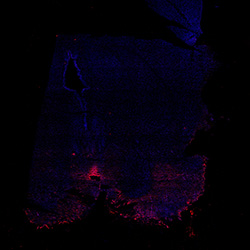

Merged

6PCW human midbrain